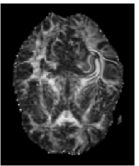

Trace and Mean Diffusivity: The total diffusivity is , and the mean diffusivity (MD) is equal to one third of . The MD measure serves as an indicator of brain maturation and/or injury, and provides the overall magnitude of water diffusion independent of anisotropy [21]. The MD map is shown in Figure 4(c), where higher values of average diffusion appear brighter.

Fractional Anisotropy (FA): FA serves as an indicator of the degree of water diffusion anisotropy independent of the overall water diffusion coefficient and is defined as

| (7) |

which is basically the normalized standard deviation of the eigenvalues. The values of FA vary from 0 to 1 with higher values corresponding to greater diffusion anisotropy. Figure 4(c) shows the FA map of the same slice as in Figure 4(a). The higher values of FA correspond to the WM regions containing densely packed fiber bundles that cause anisotropic diffusion by restricting water movement along the direction perpendicular to the fiber bundles.

![]() |

| (a) | (b) | (c) | (d) |